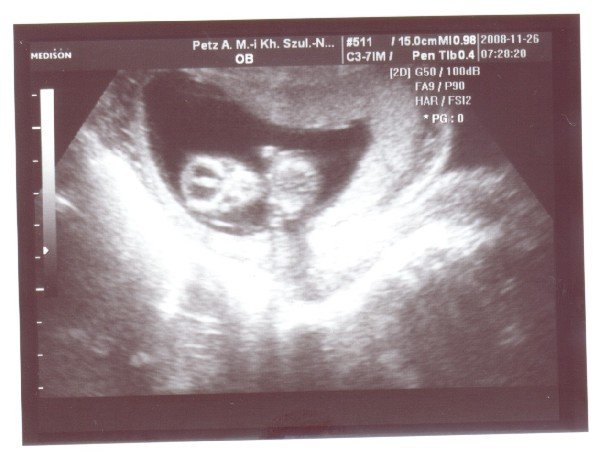

Igen, a Plázában. Nagyon úgy néz ki, hogy kisfiú :wink: , képzeld, a másik ultrahangban a te dokid volt, bár én nem hozzá kerültem....kicsit meglepődtem, hogy már látja, de a Sikovanyecz doktor nézte és ő tényleg profi....

KépKép

CSajok, bemutatom a mi kis Ufónkat :) 67 mm, NT: 1mm, és mindene megvan, annyira pörgött hogy egy ilyen "agyas" képet tudott csak csinálni a néni :)

Ja és szégyenlős volt :( na majd 2 hét múlva a 4d-n :) valahogy ki kell szednem belőle :)

Sziasztok! Megvolt ma a genetikai uh. Minden tökéletes. Nagy élmény volt. Sokat mocorgott, integetett. Gyorsan vert a szivecskéje. Szuper volt. Íme az első "igazi" babafotó: